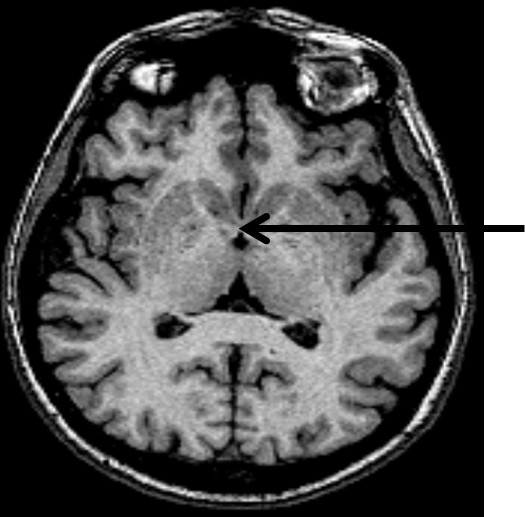

Struktura wskazana strzałką na obrazie MR to: